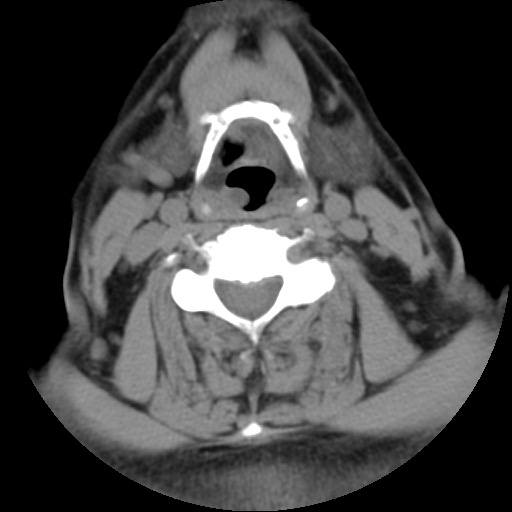

CT50903:左侧会厌谿病变?

本帖最后由 cefcmj 于 2015-7-24 12:17 编辑 患者检查颈椎间盘时发现左侧会厌谿显示欠清,无明显不适,是否为患者吞咽唾液所致,不像病变,骨质无破坏。 ...

建议喉部CT或MRI检查。